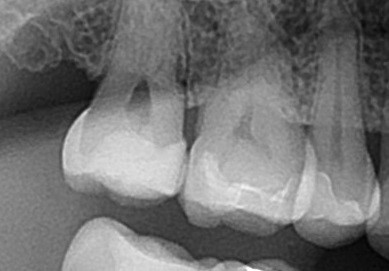

術前と術後です。

エックス線写真も比較してみてみましょう。

しっかりと密閉され、歯と一体型になっているのがわかります。他の歯にみられる、セラミックとのつなぎ目も見られません。この状態だとしっかりと接着され安心となります。